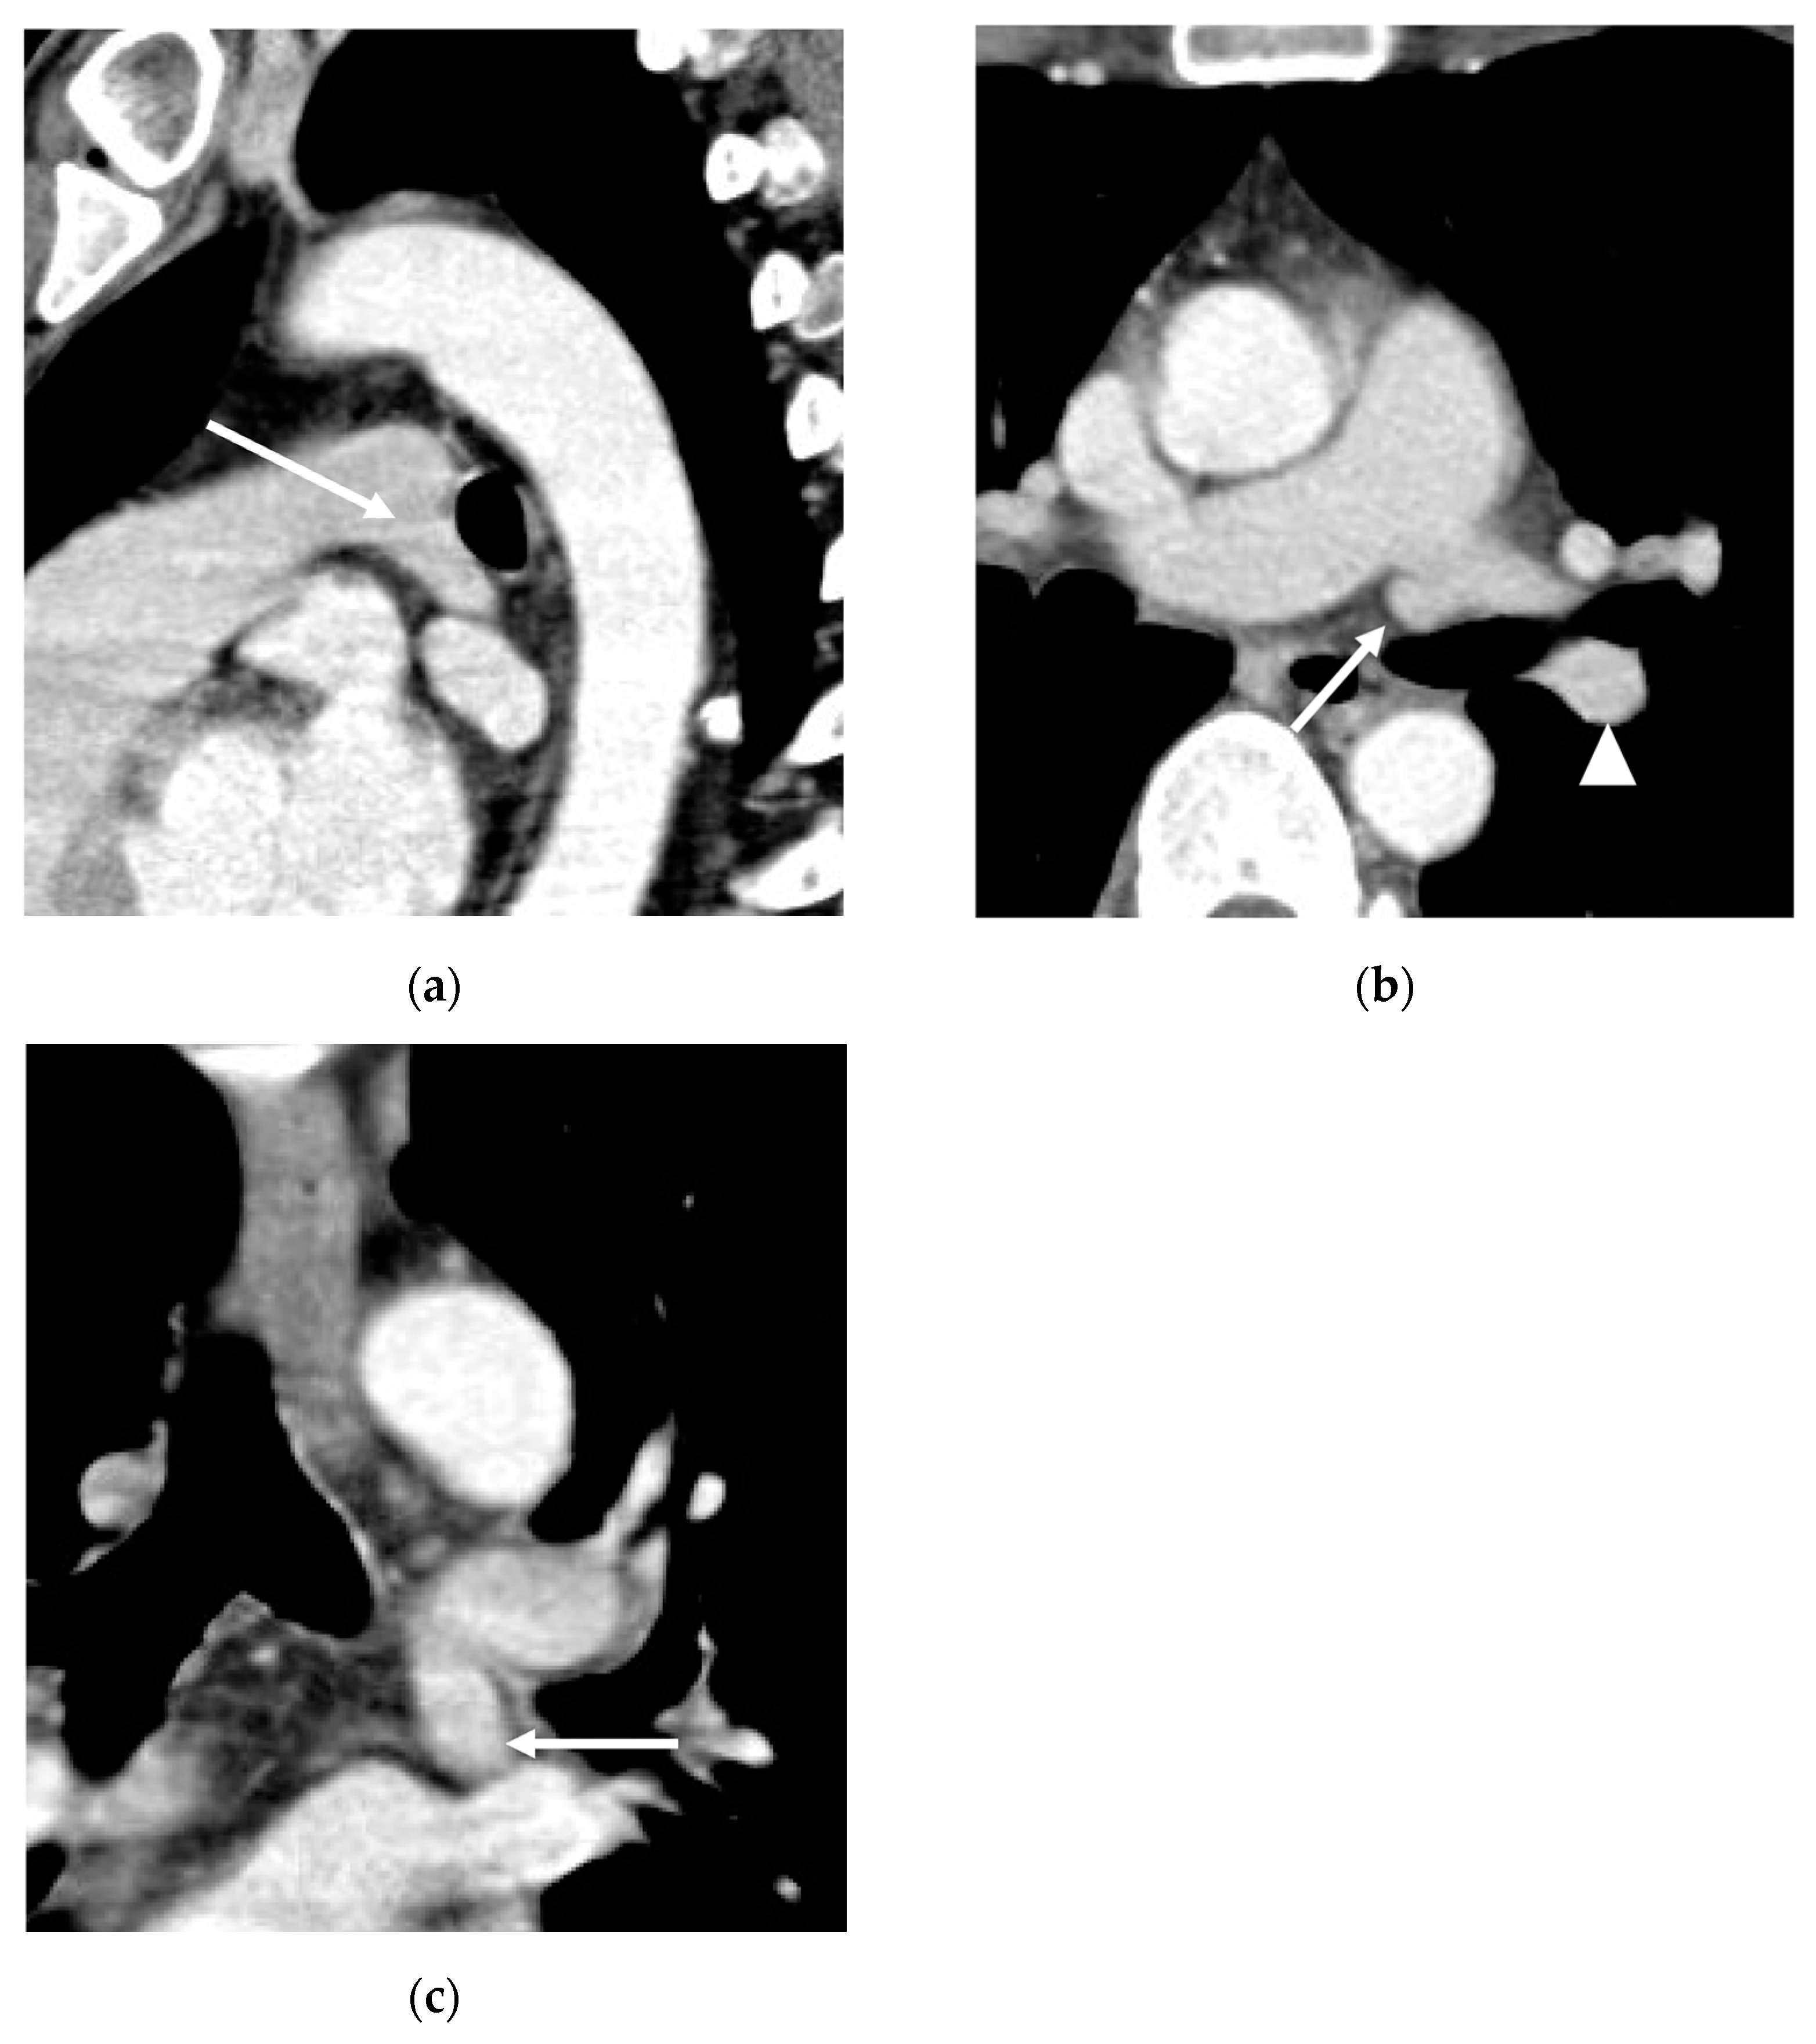

3. Results

3.3. Diameter of the AP

3.4. Presence of Other Accompanying Variations